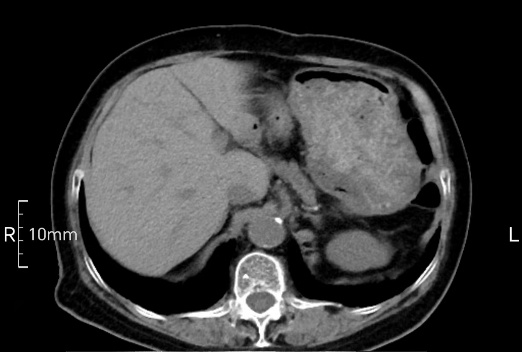

看看下面三幅便知遵醫(yī)囑的重要性。

完美禁食且喝飽飽,胃壁完美展現(xiàn)。

CT檢查前的“禁食”和“喝飽”,看似矛盾,實則合情合理,分工合作:空腹:是為了讓上腹部(肝膽胰脾腎等)的圖像清晰無干擾,并保障檢查安全。喝水:有效的充盈胃部和、腸道使圖像清晰呈現(xiàn)。兩者巧妙配合,都是為了給您一個最精準(zhǔn)的診斷結(jié)果。